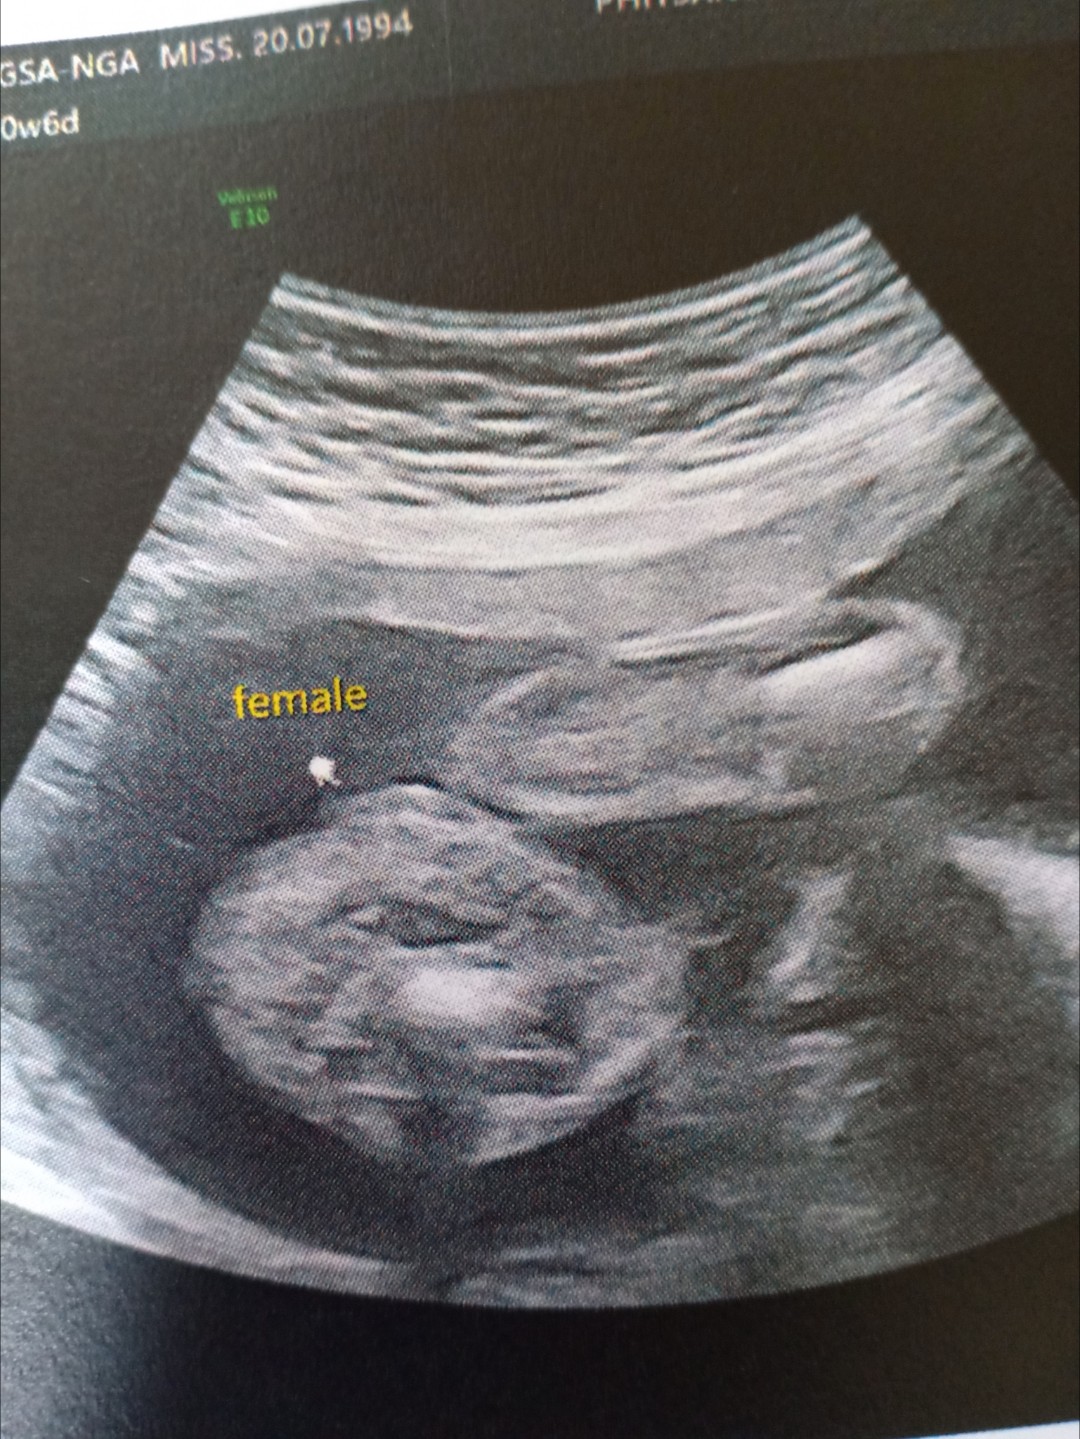

ผู้หญิงค่าา 👧 21 w

หนูมีกลีบค้าา😂

กลีบเต็มๆคะ